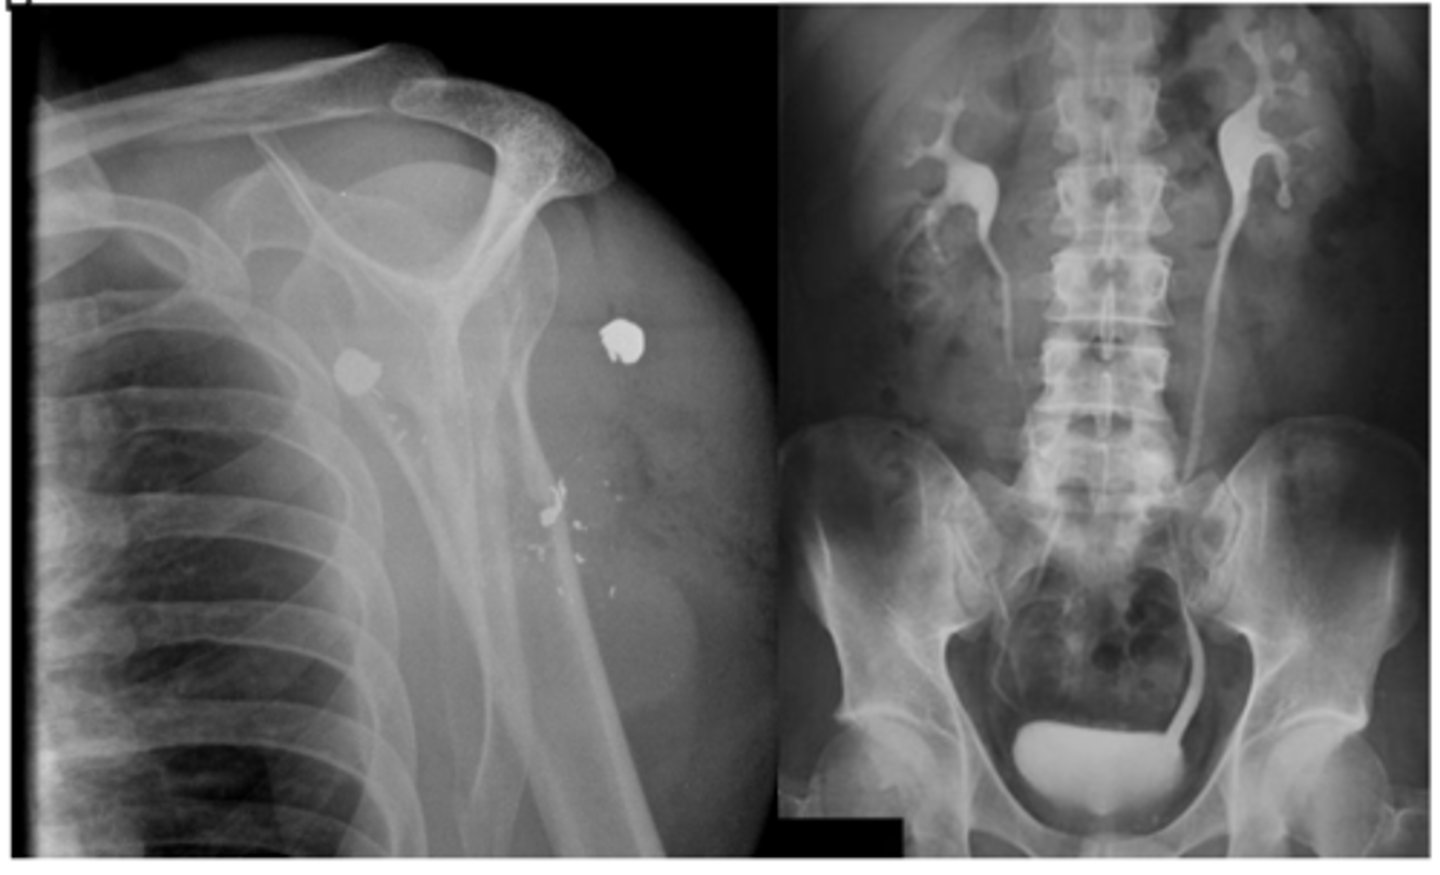

what are the three indications for hip radiograph

hip pain

avascular necrosis

stress fractures

for the pelvis what position is the hips for an AP view

IR 15-20 degrees

what are the three important portions of the acetabulum (ap view)

what position will the hip be if you want to see the medial portion of the femur (AP view)

frog leg